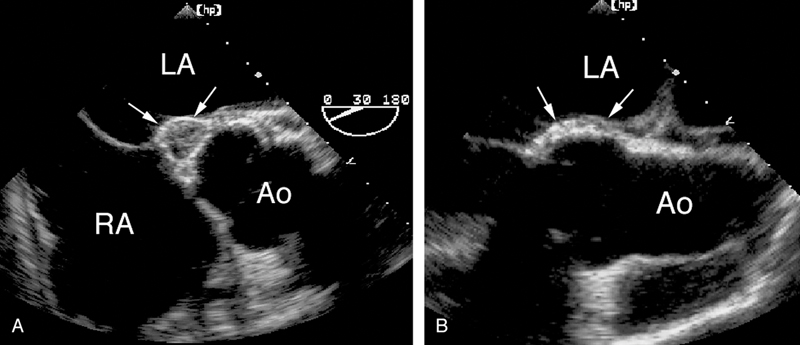

فحوصات تشخيصية لبعض امراض القلب والشرايين التاجية